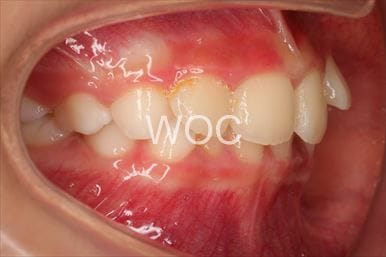

治療後1

- 年齢:20歳女性

- 主訴:出っ歯が気になる

- 基本矯正料金:120万円

- 治療期間:1年7ヶ月

- 抜歯部位:上顎両側第一小臼歯